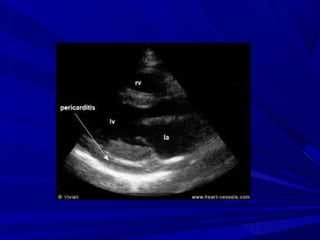

EchocardiographyEchocardiography

Normal in acute pericarditisNormal in acute pericarditis

Pericardial fluidPericardial fluid

Pericardial thicknessPericardial thickness

> 20 ml posteriorly> 20 ml posteriorly

>200ml anteriorly and posteriorly>200ml anteriorly and posteriorly

Mild < 5 mm in diastole (50-100ml)Mild < 5 mm in diastole (50-100ml)

Moderate 5-20 mm (100-500 ml)Moderate 5-20 mm (100-500 ml)

Severe >20 mm (>500ml)Severe >20 mm (>500ml)

ECHO-CARDIOGRAPHYECHO-CARDIOGRAPHY

Signs of high fluid quantitySigns of high fluid quantity

Swinging heartSwinging heart

Signs of high pericardial pressureSigns of high pericardial pressure

RA diastolic collapseRA diastolic collapse

RV diastolic collapseRV diastolic collapse

LA, LV diastolic collapseLA, LV diastolic collapse

Signs of high systemic venous pressureSigns of high systemic venous pressure

IVC distensionIVC distension

< 50% collapse in inspiration< 50% collapse in inspiration

Thick pericardium/calcifiedThick pericardium/calcified

““Small ventricles”Small ventricles”

““Big atria”Big atria”

IVC distension, hepatic veins distensionIVC distension, hepatic veins distension